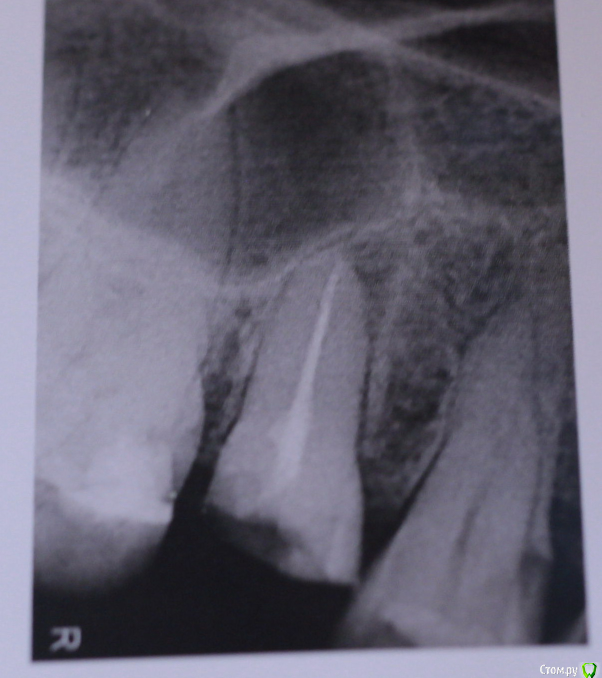

Absolute Опубликовано 22 января, 2020 Поделиться Опубликовано 22 января, 2020 (изменено) Доброго вечера! Не знаю, в какой раздел писать, пишу сюда. Очень прошу совета.Проблема - сломался зуб. 15-й (я не знаю точно, когда делали снимок, произносили это). Почти пополам, корень целый. Пошла к стоматологу, надеялась на реставрацию штифтом и коронкой, но врачи (терапевт, хирург и ортопед) сказали - удалять и ставить имплант. Удалять, т.к. киста и в любой момент зуб может заболеть, а значит коронка и штифт - просто выкинутые на ветер деньги, мол, лучше не рисковать. Я пока не готова к импланту, может есть варианты эту кисту пролечить или удалить? Прикрепляю снимок. Изменено 22 января, 2020 пользователем Absolute Ссылка на комментарий

dok1 Опубликовано 22 января, 2020 Поделиться Опубликовано 22 января, 2020 Ну если небеспокоит, ставьте вкладку и коронку. Постоит ещё. По снимку всё недурно Ссылка на комментарий